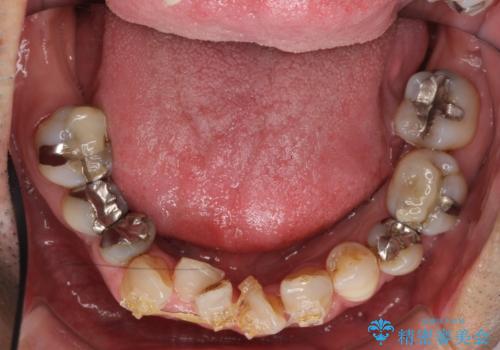

前歯の部分矯正を行い受け口を改善しました。

奥歯まで動かそうとすると顎の手術の適応になってしまうため、奥歯はそのままにして前歯のかみ合わせを改善しました。

また、奥歯はインプラント治療を行い、矯正で下の前歯を後ろに下げるのに使用しています。

通常骨格的な受け口を部分矯正でというのは不可能なことが多いのですが、今回はいろいろな条件が重ねなりお引き受け可能でした。通常は難しいです。